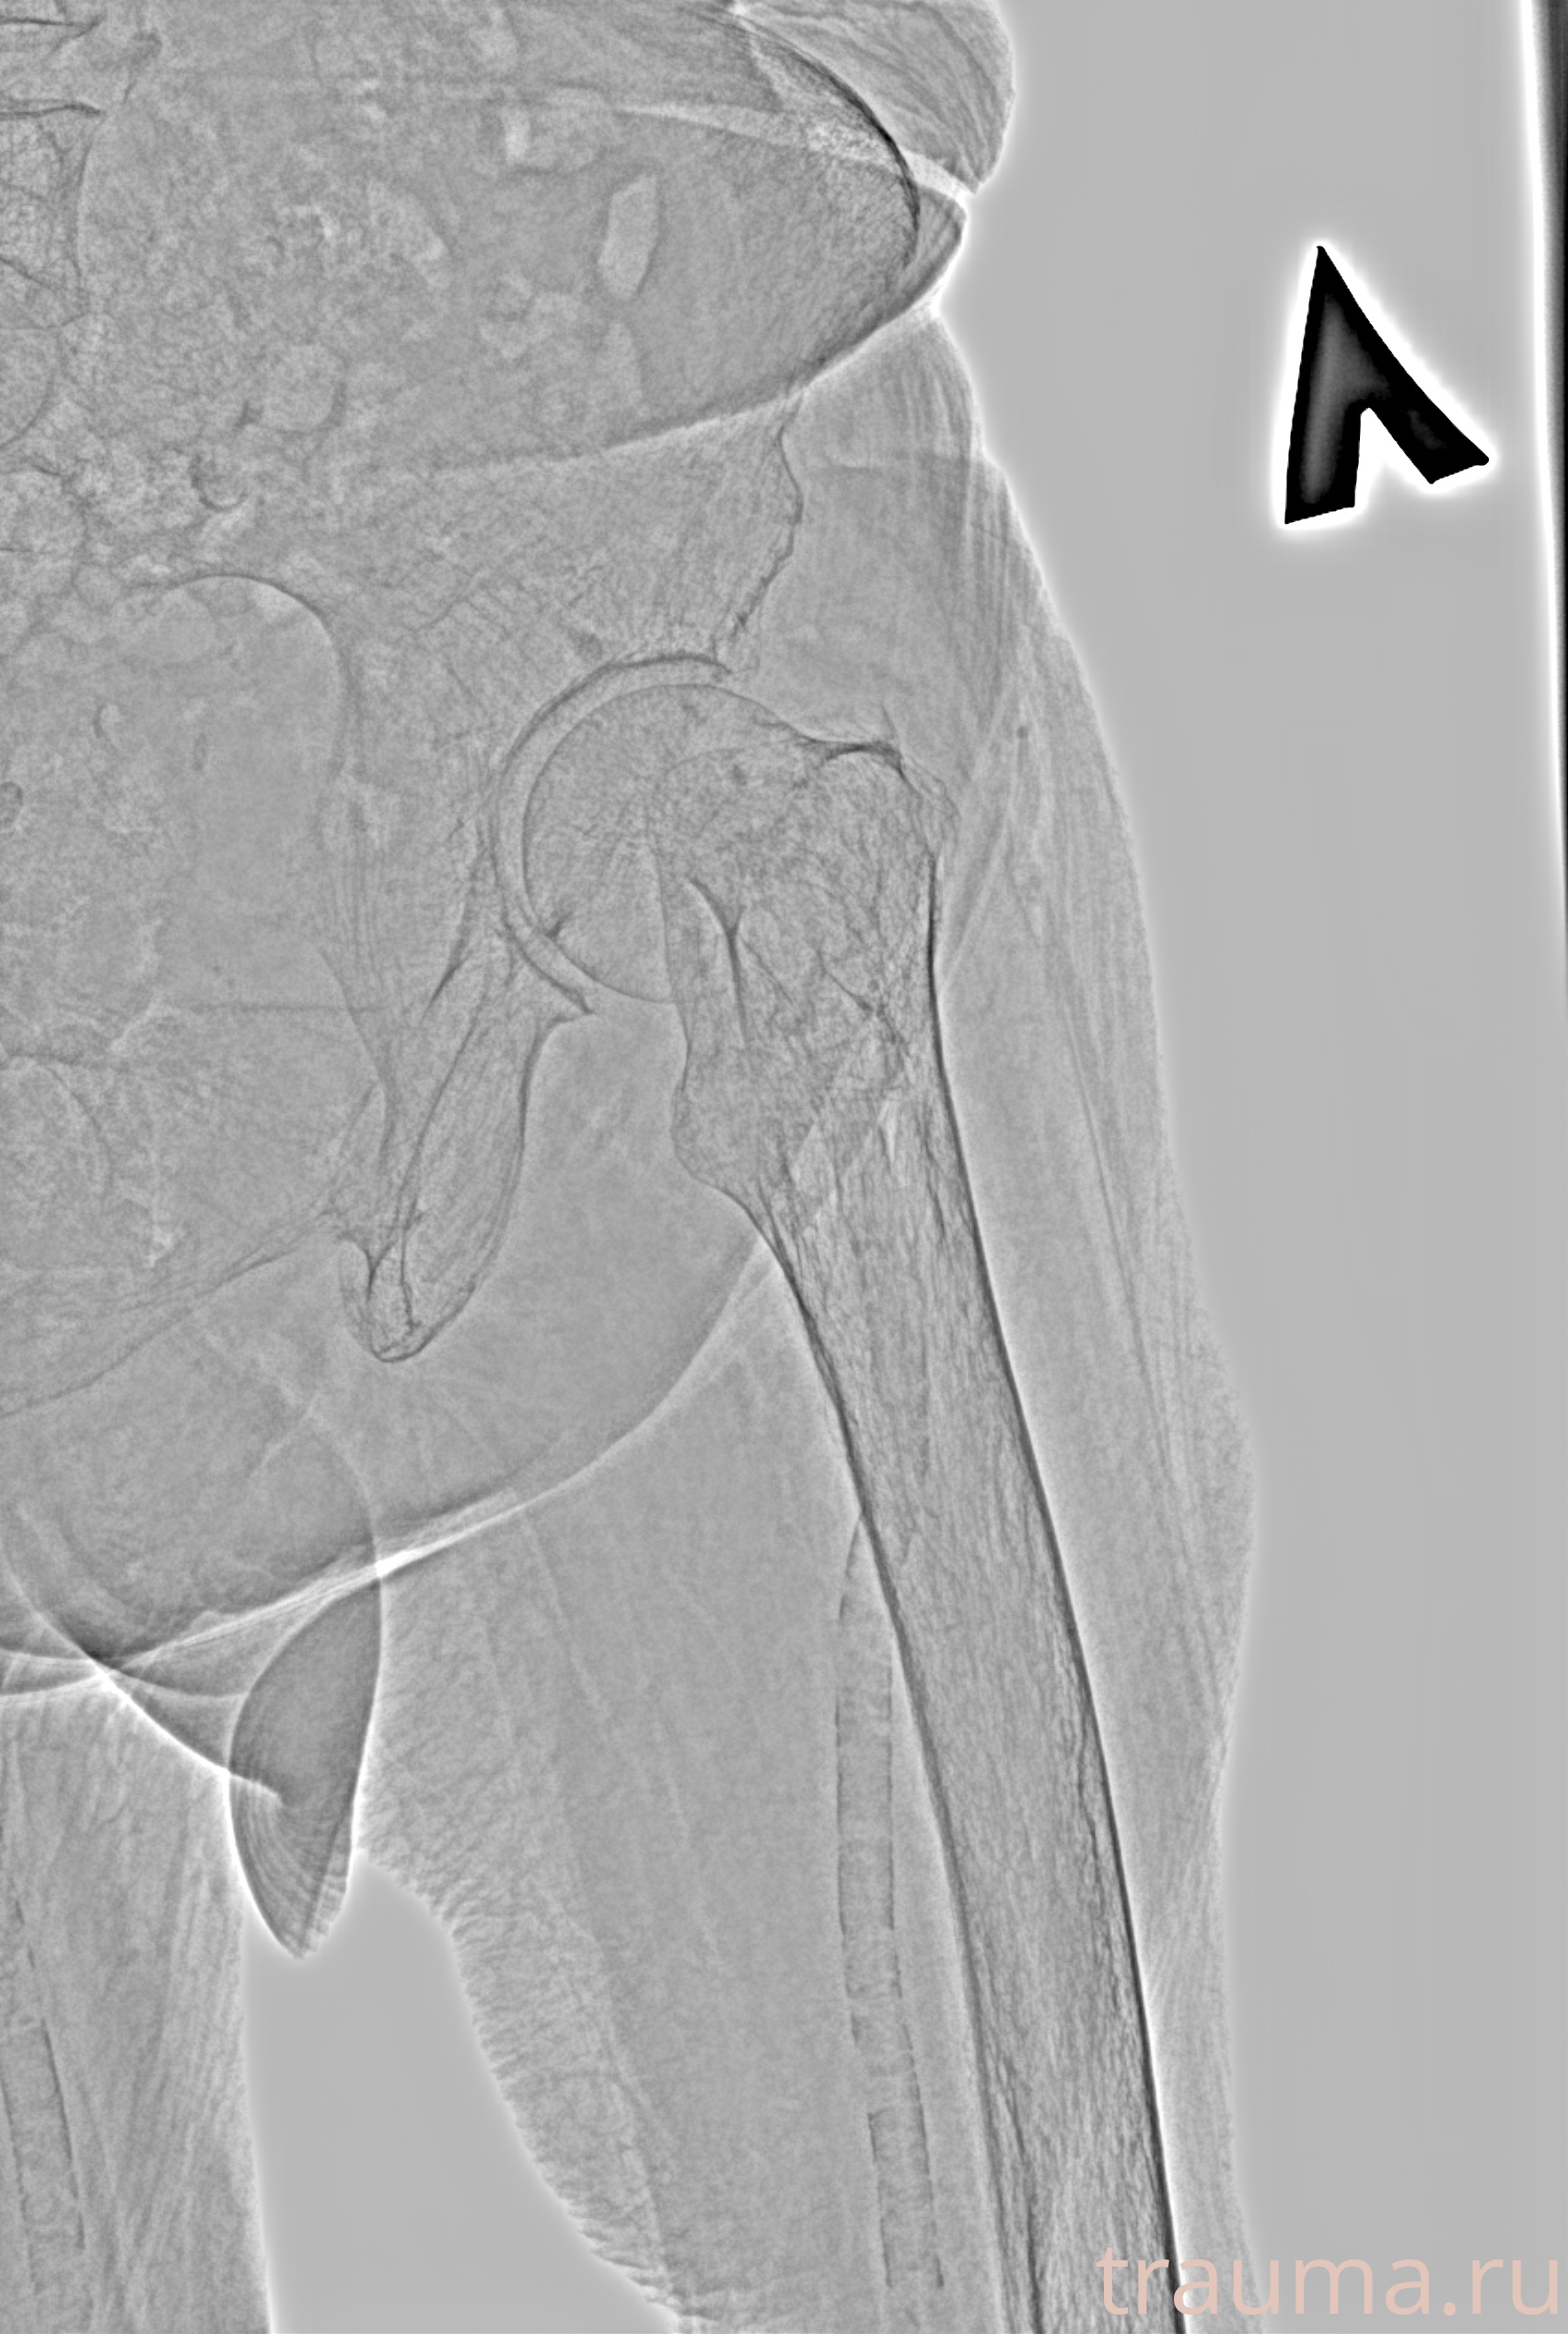

Рентген на дому: по вашему адресу приезжает врач-рентгенолог, травматолог-ортопед с мобильным рентгеновским аппаратом, проводит диагностику травмы или заболевания, делает необходимые рентгенограммы, дает рекомендации по дальнейшему лечению. Получить качественные снимки в домашних условиях возможно благодаря уникальной методике, разработанной МосРентген Центром для института  Склифосовского